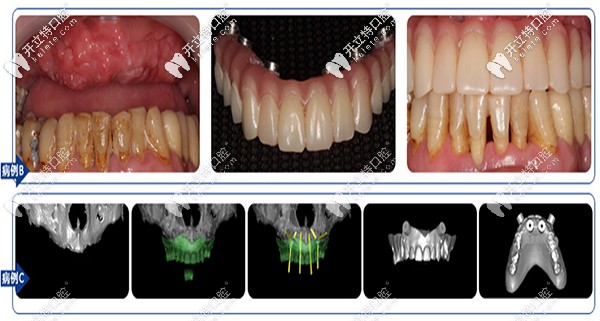

【沈陽(yáng)盛大口腔全口、半口缺失案例】

沈陽(yáng)盛大口腔全口、半口缺失案例

【沈陽(yáng)盛大口腔多顆牙缺失】

沈陽(yáng)盛大口腔多顆牙缺失

盛大口腔在種植牙方面,No belClinician軟件直觀模擬治療方案、種植導(dǎo)板定制,2小時(shí)戴牙,即可解決牙齒缺失。